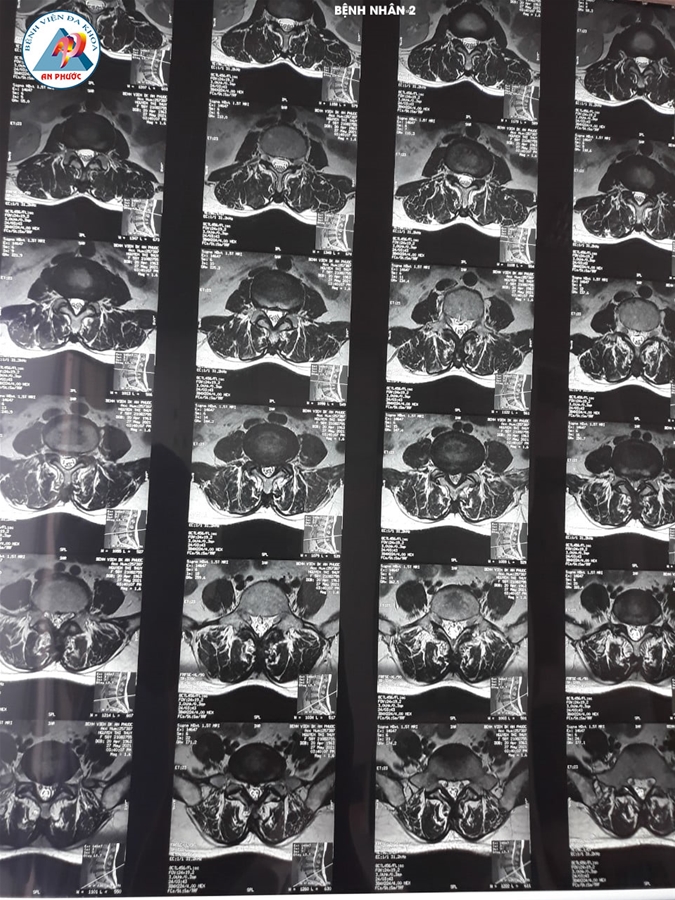

Trường hợp 2: Bệnh nhân nữ, 58 tuổi, ngụ tại Bảo Lộc - Lâm Đồng. Vào viện với tình trạng đau lưng, tê bì chân phải. Bệnh nhân có điều trị nội khoa và tập vật lý trị liệu hơn 06 tháng, nhưng bệnh không giảm.

Qua thăm khám lâm sàng và chụp MRI, XQ CSTL với kết quả: Thoát vị đĩa đệm L4-L5, kèm theo loãng xương nên được chỉ định phẫu thuật lấy nhân đệm và làm cứng L4-L5 bằng nẹp vis, thay đĩa đệm nhân tạo.